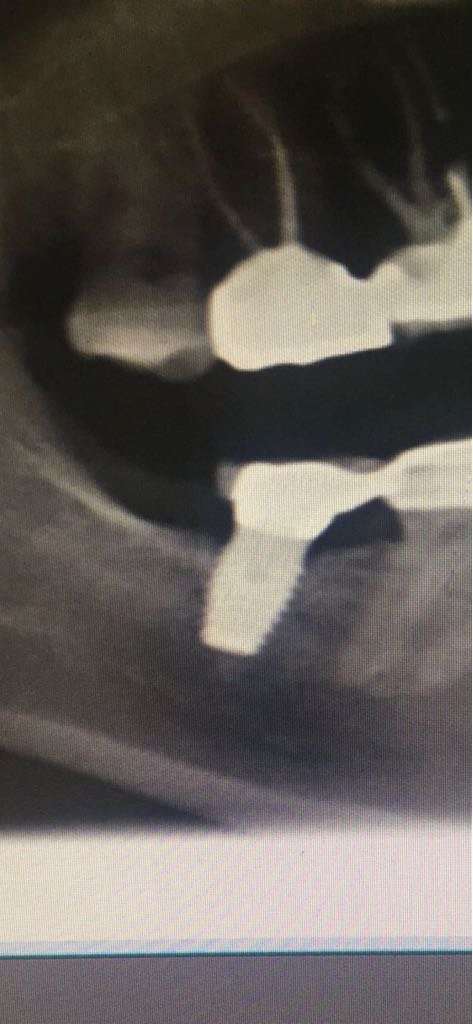

Buenos días compañeros. Alguien sabría decirme qué implantes son los que se ven en la radiografía? Muchas gracias